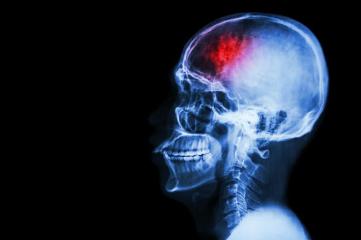

Когда у человека случается инсульт, приток крови к мозгу прерывается, что вызывает смерть клеток мозга из-за недостатка кислорода. На это уйдет всего несколько минут. В некоторых случаях это у больных возникает паралич или проблемы с речью и зрением и потере памяти. В новом исследовании ученые показали, что лечение стволовыми клетками грызунов с повреждением мозга повышает создание нервных клеток в результате инсульта.

Инсульт прерывает приток крови к мозгу, что может вызвать паралич, проблемы с речью и другие нарушения.